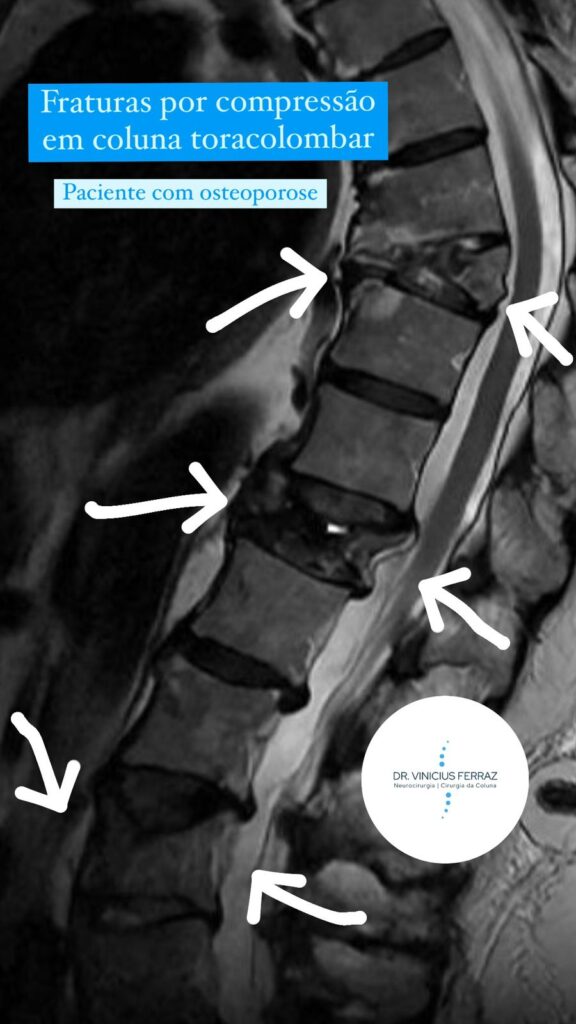

Vale lembrar que muitas vezes as fraturas da coluna toracolombar, principalmente as fraturas por compressão, resultam de um osso mais frágil, a osteoporose (enfraquecimento do tecido ósseo), e apresentam um mecanismo de lesão geralmente por traumatismos de baixa energia, como quedas e escorregões. Nesses casos as fraturas acometem mais as mulheres e com idade mais avançada, após a menopausa. Ainda existem as fraturas por compressão resultantes de tumores na coluna.